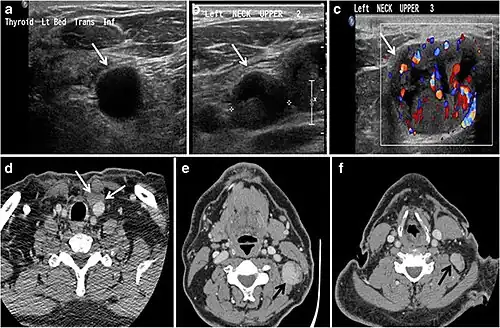

Fig. 9. A 58-year-old male patient with persistence PTC at thyroid bed with hypervascular nodal metastasis. a–c Transverse greyscale and colour Doppler neck ultrasound demonstrate hypoehoic soft tissue in the left thyroid bed (white arrow in a). There are a heterogeneous enlarged lymph nodes at level 2 and 3 with markedly increased vascularity (white arrow in b and c). d–f Enhanced axial CT images of the neck demonstrate a 2.7 × 1.4 cm hypodense soft tissue lesion anterior to the left carotid sheath (white arrow). There are left-sided enhancing abnormal and enlarged lymph nodes at cervical level 2 and 3 (black arrows).[1]

The likelihood of positive anatomic imaging is greater when serum Tg is >10 ng/mL. A diagnostic CT scan adds additional value to neck US in detecting central compartment macro-metastases in the mediastinum and retro-tracheal area. According to the recent American Thyroid Association guidelines, an upper chest and neck CT scan with IV contrast should be obtained when: 1) neck US is inadequate in visualizing possible local nodal disease (high Tg, negative neck US, and RAI imaging); 2) US is not able to delineate the disease completely, as in the case of bulky recurrent nodal disease; or 3) evaluation of possible recurrent invasive disease is needed (Figs. 7, 88 and and9).9). CT scans are also the most sensitive diagnostic tool for the detection of pulmonary micro-metastases. Many of the neck US features that are considered as suggestive signs of disease recurrence are also applicable to CT examination. These signs might include sizable rounded nodules in the thyroid bed, fine calcifications, or cystic change.[1]

Fig. 7. A 51-year-old female patient post total thyroidectomy for PTC with elevated thyroglobulin measurement. an Axial non-enhanced CT scan of the neck at the level of the thyroid bed demonstrates a well-defined, rounded, homogenously dense soft tissue situated between the trachea and left internal jugular vein (white arrow). b Transverse ultrasound image of the neck demonstrates a well-defined, homogeneous, hypoechoic soft tissue nodule measuring 6 mm (white arrow) with no detected micro-calcifications. Biopsy showed a predominantly residual normal thyroid tissue with micro-foci of PTC.[1] -

Fig. 8. A 48-year-old male patient post total thyroidectomy with PTC recurrence. a Transverse greyscale ultrasound of the neck demonstrates a left thyroid bed heterogeneous, predominantly hypoechoic irregular lesion with calcifications (white arrow). b A spot image of iodine 123 total body scan of the neck demonstrate a focus of abnormal radiotracer uptake at the left thyroid bed (Black arrows) between the annotated markers. c Enhanced axial CT scan of the neck demonstrates an enhancing large left thyroid bed mass (white arrow) with no calcifications. The lesion exerts a mass effect on the oesophagus (black arrow) and is inseparable from the trachea.[1] -